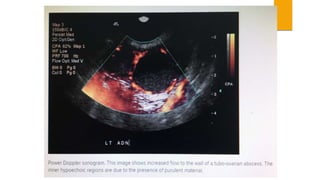

 SONOGRAPHY- Dilated and fluid-filled tubes, fluid in the pouch of

doughlas or adnexal mass are suggestive of PID.

 SONOGRAPHY- Dilatedand fluid-filled tubes, fluid in the pouch of doughlas or adnexal mass are suggestive of PID.  CULDOCENTESIS- Aspiration of peritoneal fluid and its white cell count, if exceeds 30,000/mL. is significant in acute PID. Bacterial culture from the fluid is not informative because of vaginal contamination.